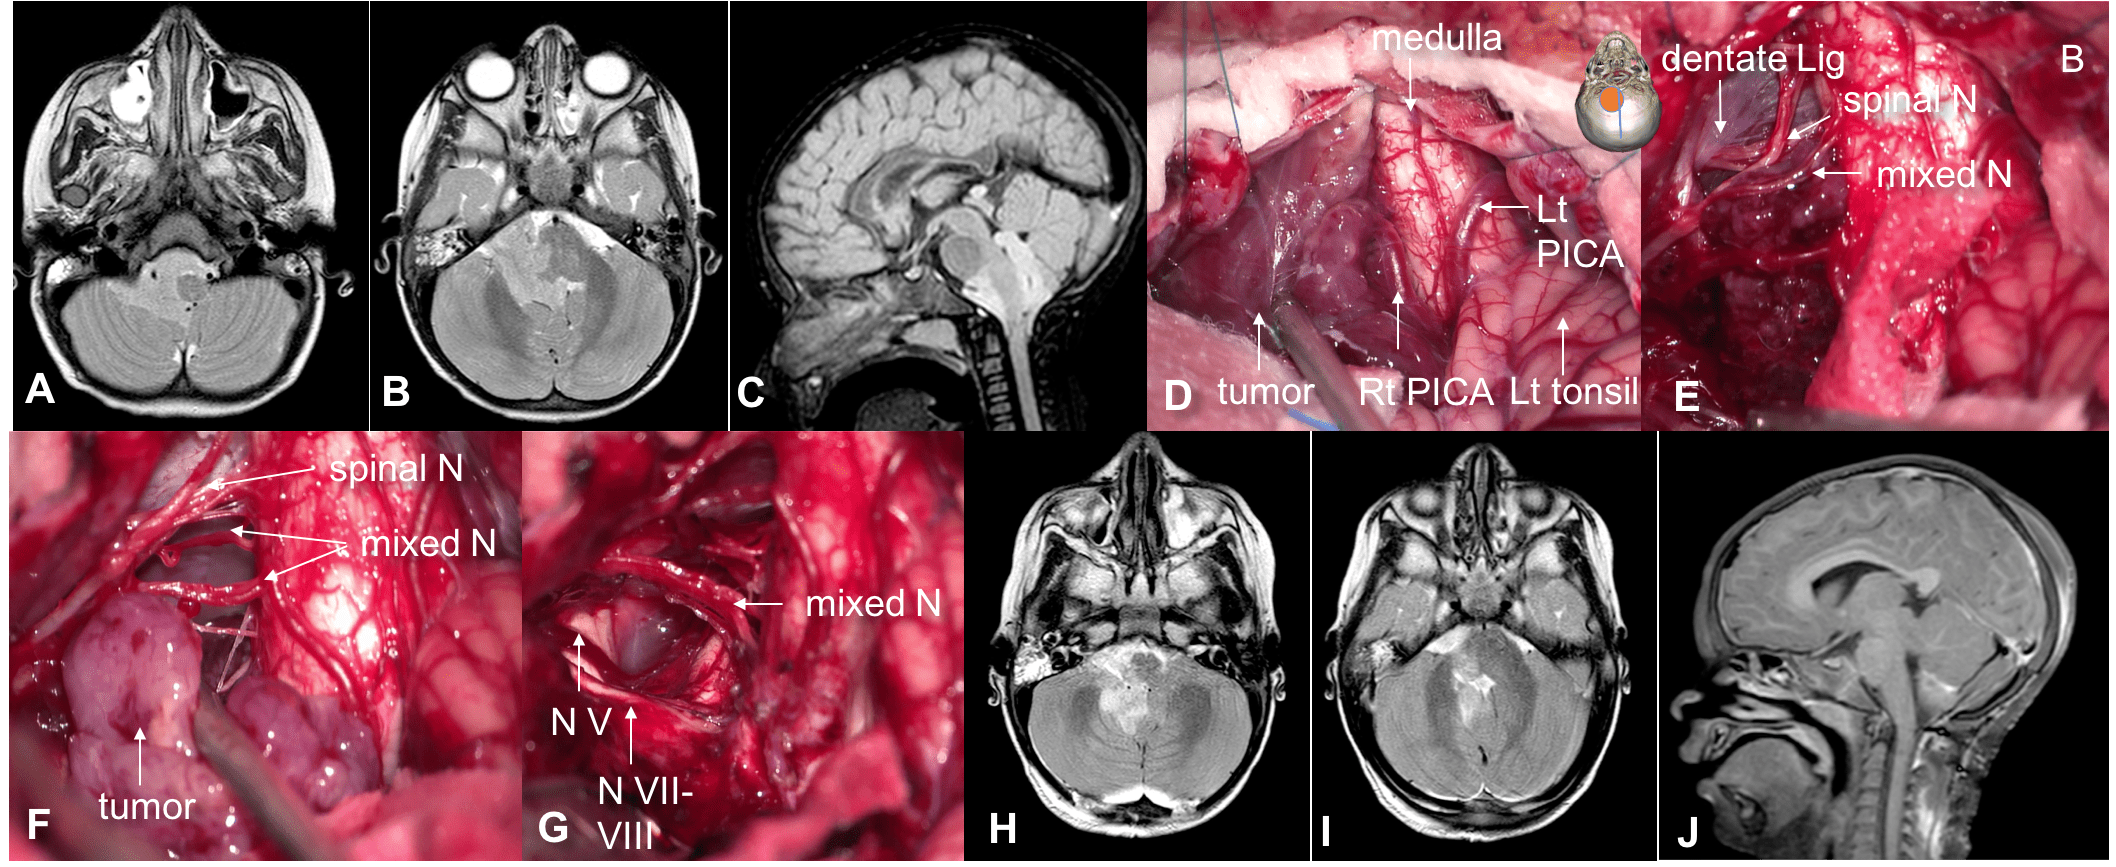

la voie inter-télo-vélaire

l’accès au quatrième ventricule se fait par une dissection inter-télo-vélaire méticuleuse qui permet d’ouvrir largement le ventricule, de contrôler le toît du V4 et d’exposer largement l’aqueduc. celle-ci commence par une dissection arachnoïdienne de la tonsille, qui se continue en la séparant de la PICA, puis on coagule et sectionne le velum interpositum. on contrôle ansi la toile choroïdienne et les afférentes vasculaires de la tumeur qui s’y trouvent.

l’abord de l’angle ponto-cérébelleux

la dissection cisternale de l’angle ponto-cérébelleux peut être difficile du fait de l’agressivité de la tumeur envers les nerfs mixtes (ATRT+++), du saignement de veines en pont (veine de Dandy) ou des sinus duraux (golfe jugulaire).

il permet néanmoins un contrôle satisfaisant de nerfs crâniens III à XII, de l’artère vertébrale et de la jonction vertébro-basilaire et de l’artère basilaire